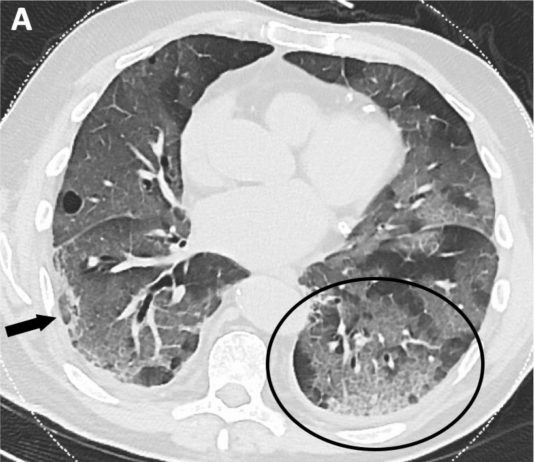

80-year-old male...